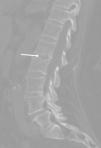

Como origen de todo el cuadro infeccioso, se barajó la posibilidad de espondilodiscitis fúngica dada la sintomatología previa de dolor lumbar que refirió y los factores de riesgo que presentaba la paciente. Las pruebas realizadas en este sentido no fueron concluyentes. Durante su ingreso en nuestra unidad se realizó TC lumbar que mostró alteración en el disco L1-L2 con erosiones en los platillos vertebrales y esclerosis en los cuerpos vertebrales indicativa de espondilodiscitis (fig. 2). Al no poder completar estudio con resonancia magnética, ya que lo contraindicaba el recambio valvular reciente, se decidió realizar gammagrafía con galio 67 que mostró la presencia de un discreto depósito de galio en la columna lumbar (L1-L3), correspondiente con la presencia de un foco infeccioso o inflamatorio (degenerativo). Ante los hallazgos de hemocultivos seriados negativos y como se iba a mantener el tratamiento antifúngico de forma crónica, se decidió actitud conservadora y seguimiento4–7. Varios meses después del alta hospitalaria se realizó una TC lumbar de control donde básicamente se observaban los mismos cambios que en el previo.